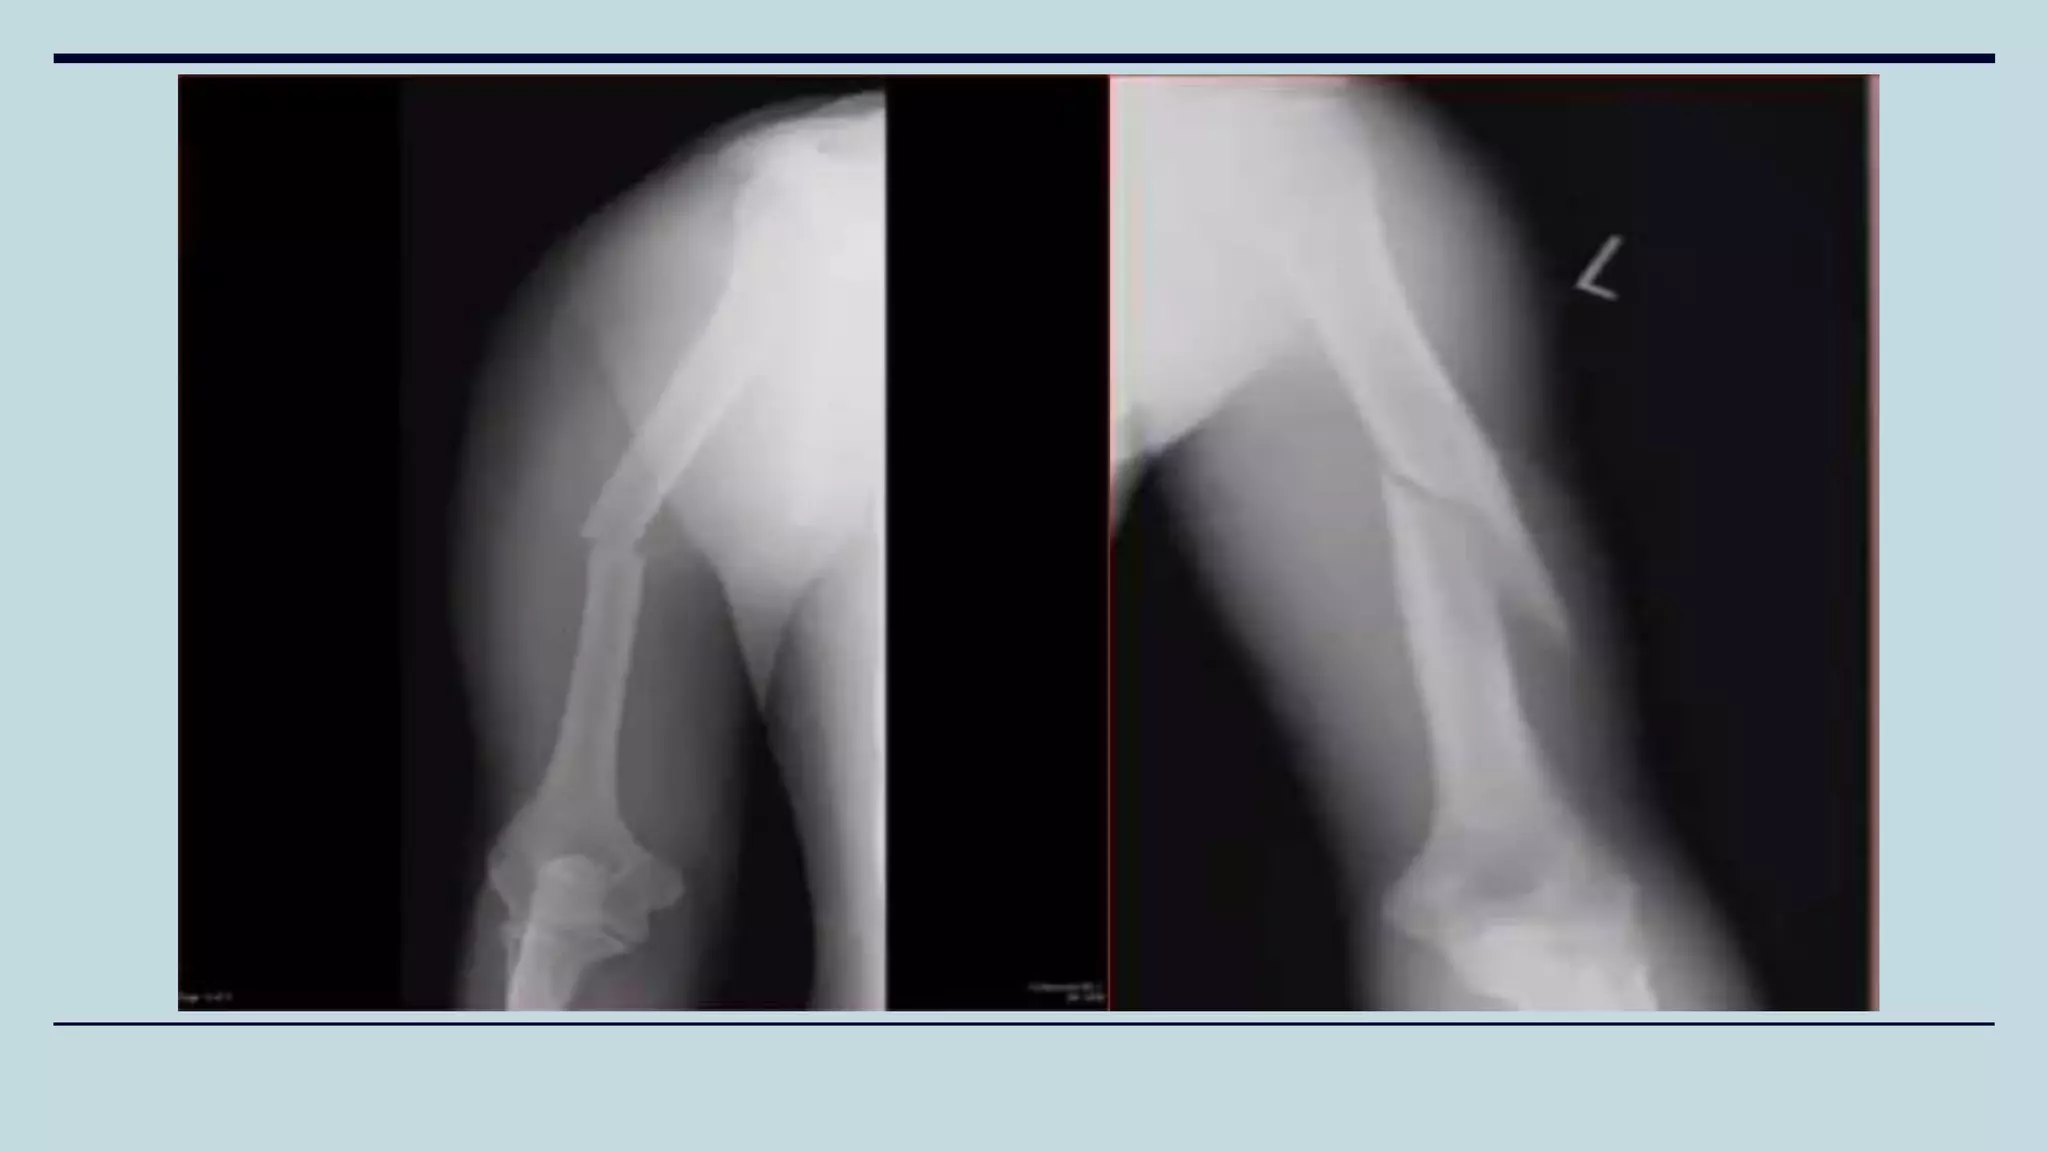

Humeral Shaft Fractures

• Fracture of diaphysis of the humerus

• Causes: Usual cause is direct trauma/Fall on an outstretched hand

• Fracture pattern depends on the stress applied.

• Symptoms: Pain, swelling, decreased ROM

• Examination: Assess Neurovascular status. Most commonly the radial nerve is affected

(Supplies motor innervation to the wrist extensors causing wrist drop)

Holstein-Lewis Fracture

• Distal 1/3 fracture of Shaft of Humerus

• May entrap or lacerate radial nerve as the

fracture passes through the intermuscular

septum